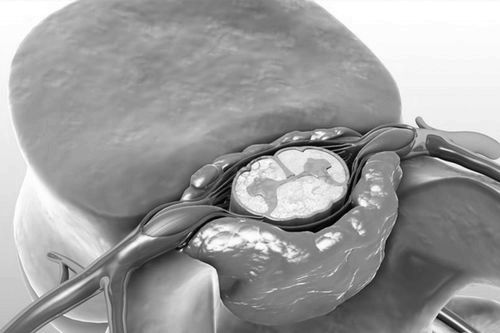

Защемлення нерва між хребцями

У тому випадку якщо описані методи не приводять до зникнення симптомів або якщо лікувати захворювання такими шляхами марно через тиск кровоносної судини на нерв, пацієнту показана мікроваскулярная декомпресія - операція, яка полягає в установці тефлонового або іншого синтетичного протектора між ураженим нервом і тиснуть на нього кровоносних посудиною.

Це радикальний метод, що дозволяє повністю (в більш ніж 80% випадків) або, в менш вдалих ситуаціях, частково усунути причину і симптоми невралгії.

Слід пам'ятати, що вищеописаний метод застосовується в крайньому випадку і пов'язаний з найбільшим ризиком. Смертність при цьому становить близько 0,1% від числа прооперованих, інсульт розвивається в одному відсотку випадків, ще невелика частина пацієнтів (близько 3%) ризикує втратити слух.